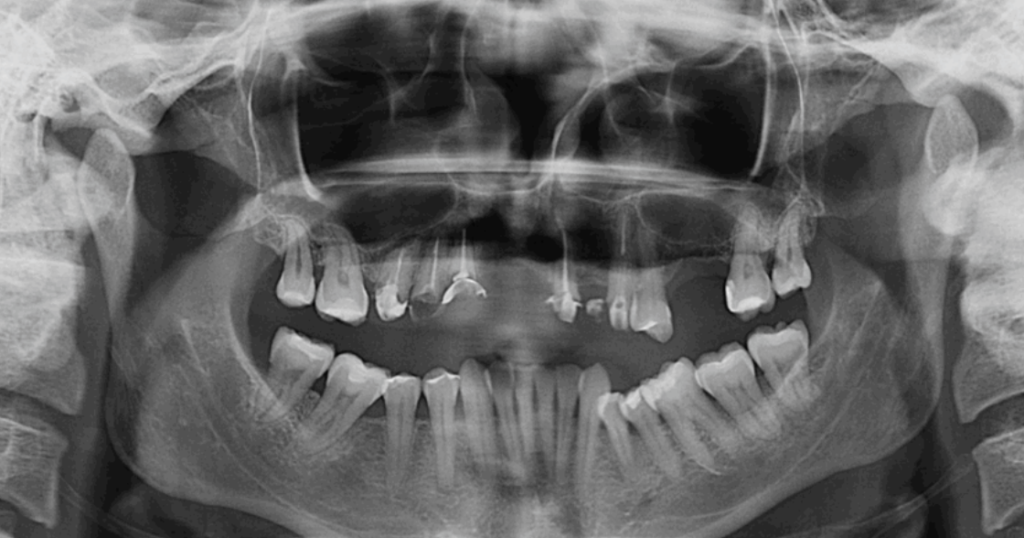

Ante una fractura dental, el tiempo es clave. Acudir pronto al dentista puede marcar la diferencia entre salvar el diente o perderlo. El uso de radiografías y estudios clínicos detallados permite tomar la mejor decisión.